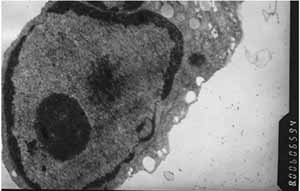

![毒藥[藥物] 毒藥[藥物]](/img/c/828/nBnauM3XwMjN4QDMwQDNzYTO5MTM4QDN3ETNyQTNwAzMwIzL0QzL2IzLt92YucmbvRWdo5Cd0FmLxE2LvoDc0RHa.jpg)